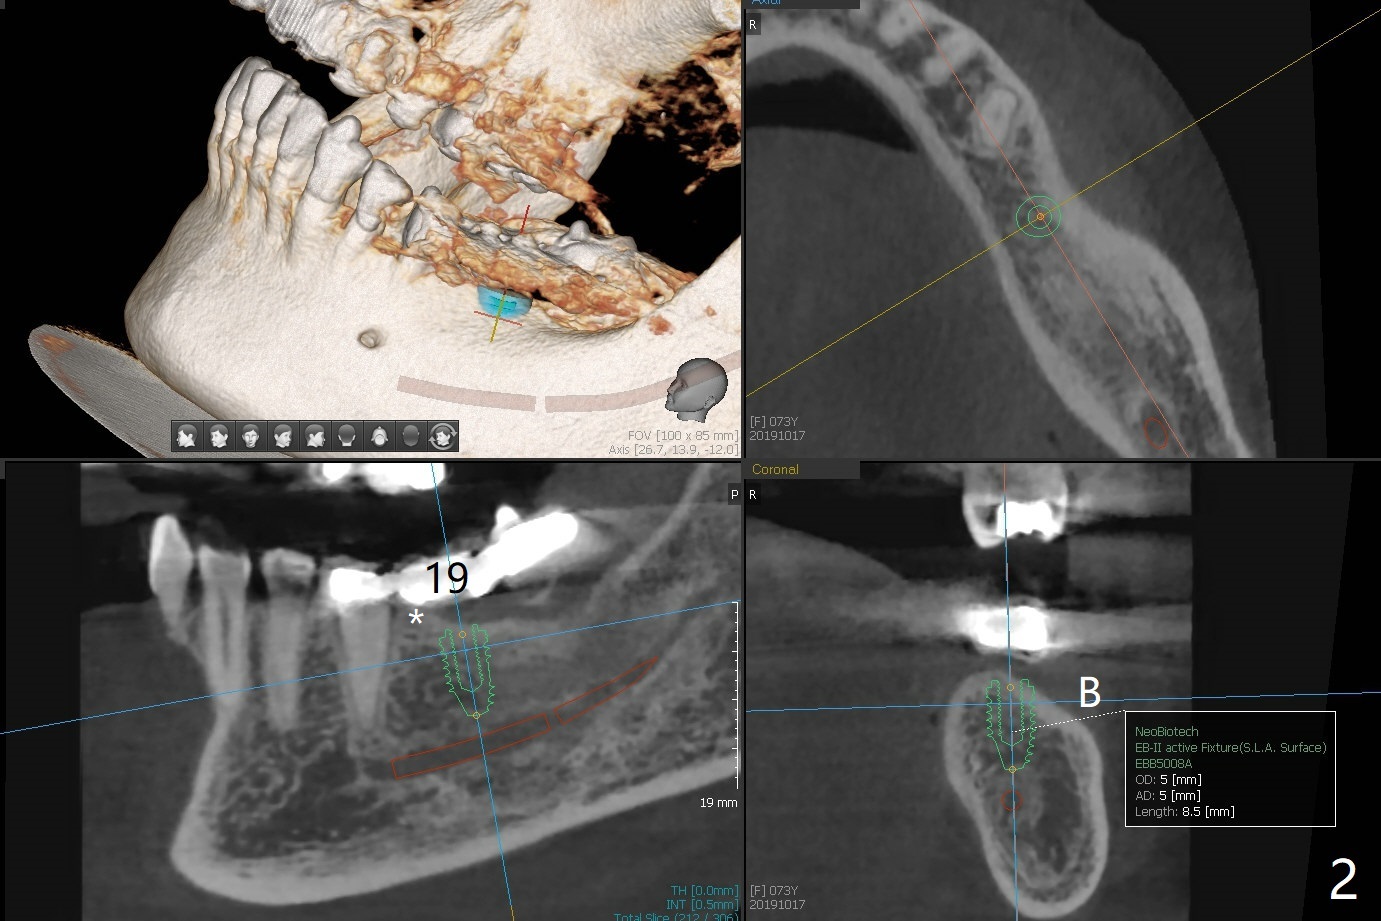

A 73-year-old woman has interest in implants at #19 and 29 (Fig.1). The ridge is not even, higher mesio(*)lingually (L, Fig.2,3). After implant placement, use profile drill (5.5 or 6.0 mm) to facilitate healing abutment placement.